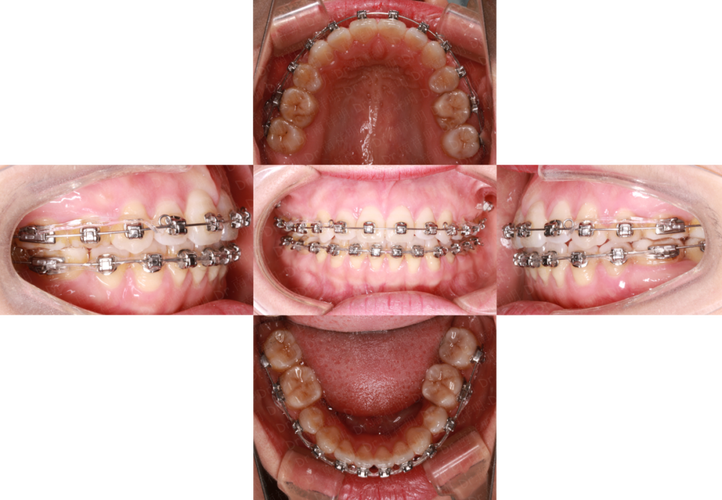

主动治疗是开合矫正的核心,需根据病因选择不同矫治器(传统金属托槽、陶瓷托槽、隐形矫治器等),分阶段完成:

- 模型分析:制取口内石膏模型,测量上下牙弓宽度、长度、Spee曲线深度,分析牙齿倾斜度及拥挤度。